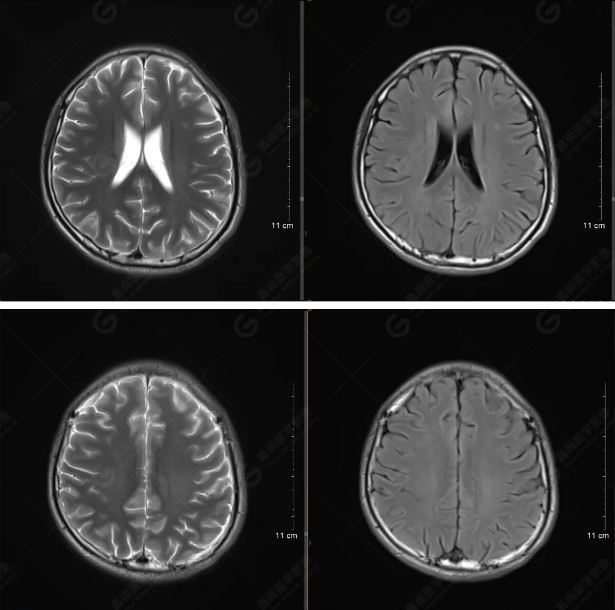

(左側(cè)為薄層原始圖像,右側(cè)為后處理5mm圖像)

SWI序列影像表現(xiàn)及診斷

左側(cè)額底及左側(cè)顳葉內(nèi)見多發(fā)斑點狀極低信號影??紤]額顳葉多發(fā)腦挫傷伴微出血、含鐵血黃素沉著,左側(cè)乳突骨折、乳突內(nèi)積血。討論:1、SWI利用不同組織間磁敏感的差異成像并將其放大,通過檢測病灶中的靜脈分布、出血灶和礦物質(zhì)沉積等,有效改善了相關(guān)疾病的診斷,主要應(yīng)用于中樞神經(jīng)系統(tǒng)。2、根據(jù)磁距圖像和相位圖像表現(xiàn),對于鑒別顱內(nèi)出血及鈣化有一定程度的價值,用于彌補(bǔ)MRI對鈣化顯示的不足。